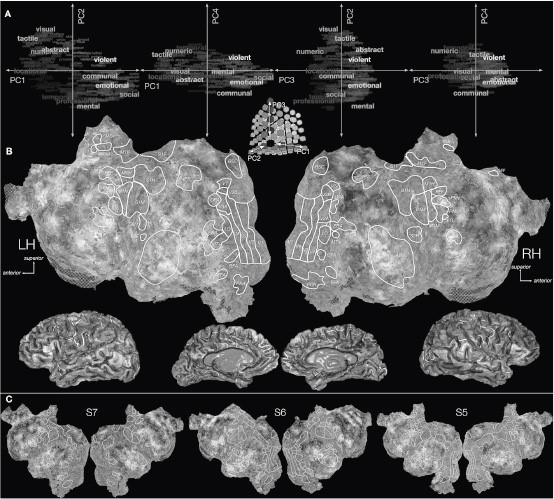

Исследователи смогли выделить 12 категорий, на которые наш мозг делит слова: тактильное (кластер содержит такие слова, как, например, «палец»), визуальное («желтый»), числовое («четыре»), пространственное («стадион»), абстрактное («естественный»), временнóе («минута»), профессиональное («совещание»), жестокое («смертельный»), общественное («школа»), ментальное («спать»), эмоциональное («презираемый») и социальное («ребенок»).

А теперь давайте посмотрим на карту, которая получилась у ученых. Цветами на ней отмечены участки коры мозга, реагировавшие на разные типы слов, и мы видим, что в этом процессе была задействована ее бóльшая часть. Впечатляет, правда?

Рис. 6. Карта коры мозга, на которой выделены зоны, участвующие в обработке речи

Источник: Alexander G. Huth, Wendy A. de Heer, Thomas L. Griffiths, Frédéric E. Theunissen and Jack L. Gallant. Natural speech reveals the semantic maps that tile human cerebral cortex. Nature. April 27, 2016. doi:10.1038/nature17637